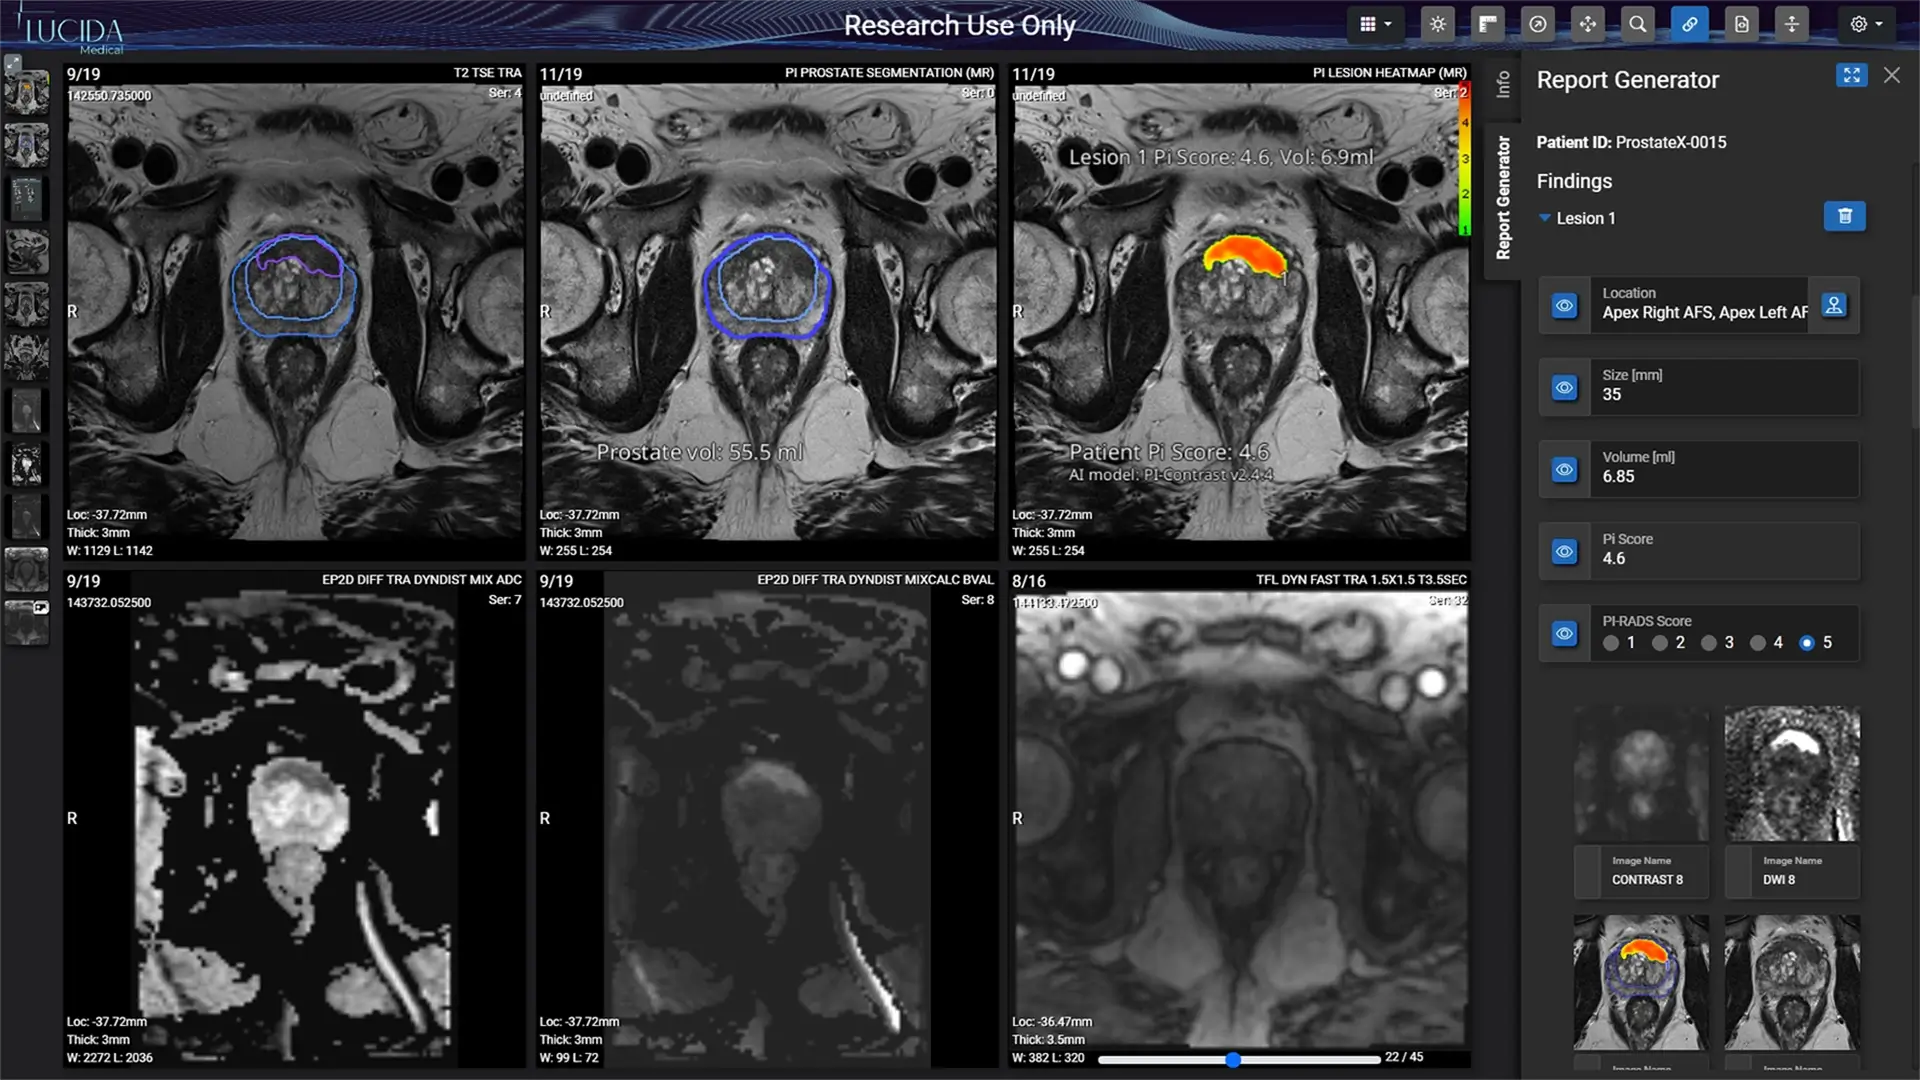

How Lucida Medical got a product update approved for their MDR-certified, prostate-cancer-detection system in one week

Lucida Medical needed a Notified Body with SaMD expertise that would enable them to consistently get the latest and best version of their ground-breaking AI system Prostate Intelligence (Pi) into the hands of users and to the patients who need it

- Developed a transformational prostate-cancer-detection system, that had already been widely deployed in the NHS

- Detects 95 out of 100 cases of clinically significant prostate cancer, with results confirmed by biopsy